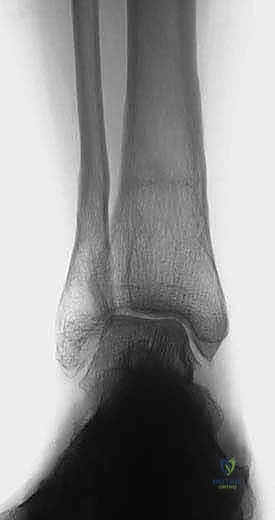

Clinical & Radiographic Imaging

Radiographic Evaluation and Imaging

Standardized imaging is the cornerstone of preoperative planning. Weight-bearing radiographs of the entire foot, the anteroposterior and lateral ankle, the tibial shaft (full-length radiographs), and the Saltzman hindfoot view are necessary to assess the nature and location of the deformity. Unless deformity at the level of the knee joint or the femur can be excluded clinically, whole lower limb radiographs are obtained to calculate the mechanical axis deviation.